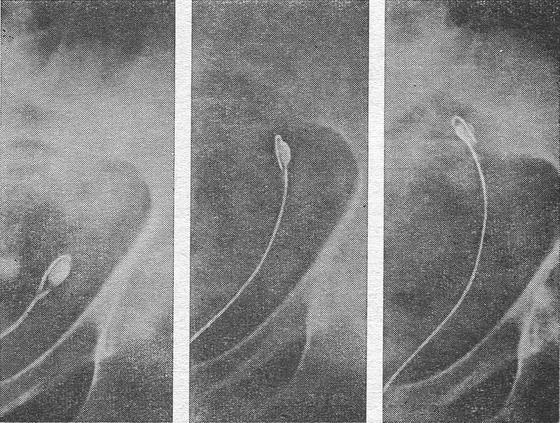

Для екстракції таких «мігруючих» каменів ми користувалися наступним способом. Підібравши петлю відповідно розмірами каменя, проводили її вище конкременту і, затягнувши приблизно на % довжини капронової нитки, залишали ' demeure на 2-3 доби. За цей час петля просувалася до рівня каменю, який зупиняється біля місця звуження, і впиралася в нього. Контроль здійснювався прицільної рентгенограмой. Якщо в цей час затягнути нитку петлі, то камінь буде щільно охоплений нею з усіх боків. При цьому краще утриматися від форсованої тракції. Принцип вичікування і обережності - обов'язкова умова, яка повинна суворо дотримуватися хірургом-урологом при цистоскопическом низведении каменів з допомогою всіх видів неметалічних екстракторів.